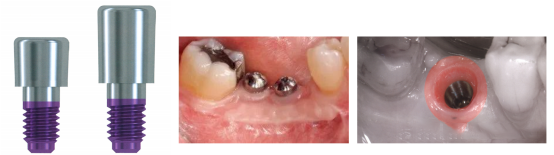

①根据种植体的平台不同愈合基台的形状也有差别,根据其形状可分为锥状愈合基台、柱状愈合基台和复合型愈合基台;

②根据其材质可分为钛金属愈合基台和Peek-聚醚醚酮愈合基台;

A:钛金属合金愈合基台具有固定的规格,厂家制作,属于成品的,不便调磨;

B:Peek愈合基台:颜色与牙齿更接近,减少取下时疼痛感,可以调磨做软组织塑性;

③根据愈合基台的加工方式:分为成品愈合基台与个性化愈合基台;

A:成品愈合基台是有厂家制作具有一定形状的大多数是金属的,具有方便快捷、可反复使用等特点;但是不便于调磨,且不是完全模拟天然牙颈部轮廓,有时会压迫唇侧牙龈而致退缩;

B:方便调磨,可进行个性化的软组织塑形,基本模拟天然牙颈部轮廓,且可以根据软组织形态进行调磨和增加;且可以诱导软组织形成良好的形态;

④大多数成品愈合基台上都有标注直径和高度,如下图某品牌种植系统的愈合基台,直径是5mm,高度(H)是5mm。